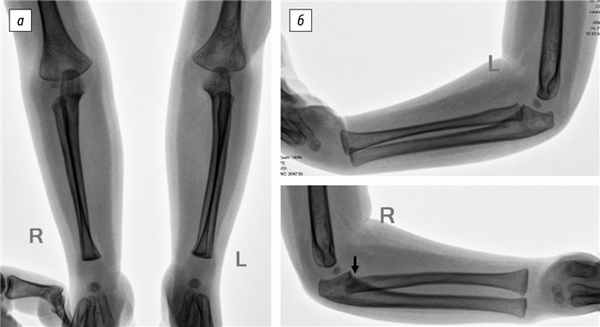

1. Рис. 1. Рентгенография локтевых суставов и костей предплечья в возрасте 4 лет. Подвывих головки правой лучевой кости (указан стрелкой): а — прямая проекция; б — боковая проекция